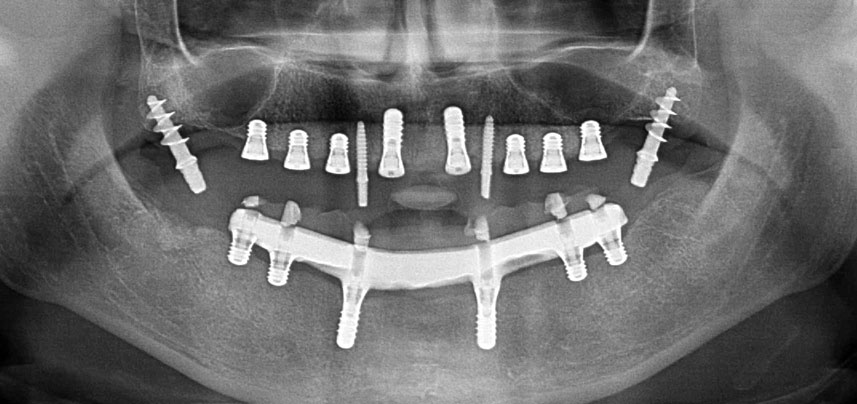

En pacientes desdentados, las prótesis fijas sujetas mediante implantes mejoran la masticación y la calidad de vida. Debido a la reabsorción y a la extensa neumatización de los senos maxilares, la paciente tenía solo una altura ósea mínima en el maxilar posterior para colocar los implantes de manera convancional. Los sitios de los implantes se prepararon con un equipo piezoeléctrico y un nuevo conjunto de instrumentos específicos. Se colocaron dos implantes de 10 mm y seis implantes de 4 mm para sujetar una prótesis fija CAD/CAM retenida con barra.

Tres años después, llegó el momento de colocar una prótesis del mismo tipo en el maxilar superior. Basándose en una planificación mediante tomografía computarizada de haz cónico (CBCT, por sus siglas en inglés), se evitó la necesidad de realizar una elevación del seno utilizando implantes cortos, mientras que una plantilla quirúrgica sirvió para transferir las posiciones planificadas al borde alveolar (figuras 1 y 2).

Debido al hueso relativamente duro (D2) existente en el sector anterior, los sitios de los implantes largos de 10 mm de las posiciones 11 y 21 se finalizaron con una fresa rotatoria de 4 mm de diámetro, en combinación con un contra-ángulo quirúrgico WS-75 L de W&H, el motor de implantes Implantmed de W&H y el módulo opcional Osstell ISQ de W&H. En cambio, debido a la existencia de hueso blando, los sitios posteriores se prepararon hasta un diámetro final de 3 mm utilizando el inserto Piezomed I3P. Por último, los implantes se colocaron a nivel crestal para su osteointegración durante tres meses (figuras 6-10). La prótesis existente se mantuvo sobre cuatro implantes provisionales (figura 8).